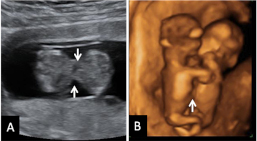

Ecografía Embarazo 4D Semana 12 - PRUEBAS DIAGNÓSTICAS